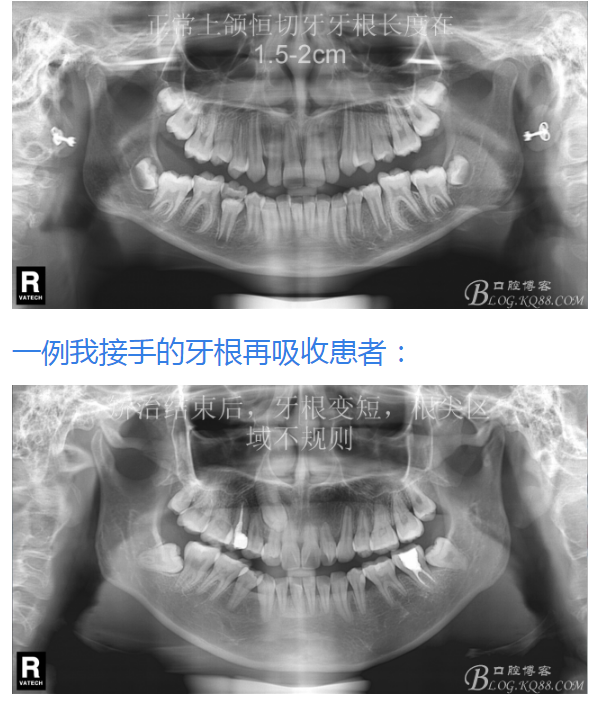

鐘佳溪:正畸治療不可忽視的副作用——牙根再吸收

有15%的人在正畸治療前就已經(jīng)發(fā)生牙根吸收,這與激素失衡和飲食缺乏有關。正畸治療后12個月,牙根再吸收的發(fā)生率增加到73%,有25%的正畸治療患者根尖吸收超過2mm,約5%的人發(fā)生超過5mm的嚴重吸收。

大多數(shù)研究認同牙根再吸收的嚴重性與正畸治療的持續(xù)時間、力量大小相關。臨床醫(yī)師應該采用輕力、高效的矯治手段進行正畸治療,并在正畸治療前、中、后進行X線檢查對比,觀察牙根再吸收的發(fā)生情況。研究發(fā)現(xiàn):間斷治療的患者其牙根再吸收量明顯少于那些持續(xù)治療的患者。應用力的中斷有助于已破壞的牙周組織重建并減少牙根的進一步縮短。